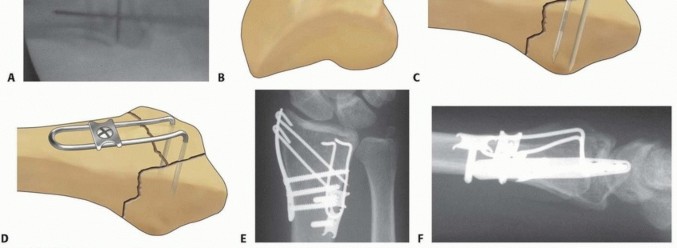

TECH FIG 4 • Volar ulnar approach. A. Incision. B. Initial exposure. C. Completed exposure. Retract the contents of the carpal tunnel to the radial side ( TECH FIG 4C). Reflect the pronator quadratus from its ulnar and distal attachment. Do not dissect more than 1 to 2 mm beyond the distal radial ridge to avoid detachment of the volar wrist capsule. 5. ## Volar Rim Fragment Small Fragment Plate Fixation Small fragment volar plate fixation may be indicated for treatment of a volar instability pattern of the volar rim. The fragment must be of adequate size to allow buttressing on the volar surface by the plate ( TECH FIG 5A,B). If volar rim fragmentation is associated with an axial instability pattern, the fragment must be of adequate size and strength to allow angular correction of the dorsiflexion deformity with distal locked screw purchase. An appropriate volar approach is used to expose the volar rim fragment. If a shortened radial column fragment is present, restoring radial length and provisionally holding with a transstyloid Kirschner wire may simplify reduction by unloading the lunate facet. Reduce the volar rim fragment; this should restore normal carpal alignment. Apply a small fragment volar plate and fix it proximally with cortical bone screws. If needed, secure the distal fragment with standard or locking bone screws ( TECH FIG 5C,D). Volar Buttress Pin Fixation Volar buttress pin fixation is indicated for unstable volar rim fragments and can be a particularly effective technique when faced with small distal fragments or axial instability patterns of the volar rim (depressed teardrop angle; TECH FIG 6A,B). Use an appropriate volar approach to expose the volar rim fragment. If necessary, restore radial length and provisionally hold it with a trans-styloid Kirschner wire to unload the lunate facet. Continue exposure for up to 1 to 2 mm beyond the distal radial ridge. Reduce the volar rim fragment as much as possible and note the orientation of the teardrop on the 10-degree lateral view. Insert two 0.045-inch Kirschner wires transverse to one another starting at an entry site 1 to 2 mm beyond the distal radial ridge. They should be placed within the center of the teardrop on the lateral view ( TECH FIG 6C). Confirm the position of the Kirschner wires with C-arm. If necessary, the volar buttress pin may be contoured with a wire bender to match the flare of the volar surface of the distal radius. Adjust the trajectory of the legs of the implant to make a 70-degree angle with the base of the wire form. Cut the legs to appropriate length, leaving the ulnar leg 2 to 3 mm longer than the radial leg ( TECH FIG 6D). Place the ulnar leg of the buttress pin adjacent to the entry site of the ulnar Kirschner wire, then remove the ulnar Kirschner wire and immediately engage the ulnar leg of the volar buttress pin into the hole. Repeat the procedure with the radial leg. Impact and seat the implant into the volar rim fragment. Apply to the proximal shaft fragment to correct any dorsiflexion of the volar rim ( TECH FIG 6E). 84

TECH FIG 5 • Volar rim fixation with small fragment plate. A,B. Shear fracture of volar rim with volar instability pattern. C,D. Fixation with small fragment plate.

TECH FIG 6 • Volar rim fixation with a volar buttress pin. A,B. Articular fracture with axial instability pattern of volar rim. C. Insertion of Kirschner wires. D. Cutting and inserting legs. E. Reduction of teardro (continued) 85

TECH FIG 6 • (continued) F. Completed fixation. G,H. Volar buttress pin fixation to control rotational alignment of volar rim fragment. Fine-tune the reduction and fix it proximally with a minimum of two screws and washers ( TECH FIG 6F-H). If needed, a blocking screw can be placed just proximal to the end of the buttress pin to prevent shortening of the fragment. Alternatively, a wire plate can be used to secure the implant proximally. Volar Hook Plate Fixation Volar hook plates are useful alternative to volar buttress pins for fixation of unstable volar rim fragments, particularly for small distal fragments associated with axial instability patterns of the volar rim or volar instability patterns associated with volar shear fractures. Expose and reduce the volar rim fragment according to the technique described for the volar buttress pin. If possible, provisionally hold the reduction with a Kirschner wire in the radial and ulnar border. Position and insert a 0.045-inch Kirschner guidewire distally down the center of the teardrop along the intended path of the hooks of the plate. Confirm the position with the C-arm. For hard bone, place a volar hook plate drill guide over the guidewire, and predrill the cortex for insertion of the hooks. In osteoporotic bone, this step may not be necessary. Insert the volar hook plate over the guide pin and seat into the distal fragment ( TECH FIG 7A-C). Place a distal locking peg of appropriate length after predrilling with a fixed-angle peg guide. Fix the plate proximally with standard bone screws.